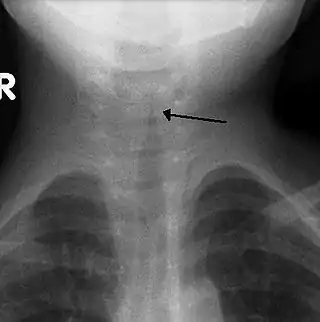

Usualmente no se realiza una radiografía frontal del cuello,[4] pero si se hace, puede mostrar un estrechamiento característico de la tráquea, llamado signo de punta de lápiz o del campanario, debido a que la estenosis subglótica tiene forma de un campanario. El signo del campanario sugiere el diagnóstico, pero está ausente en la mitad de los casos.[3]